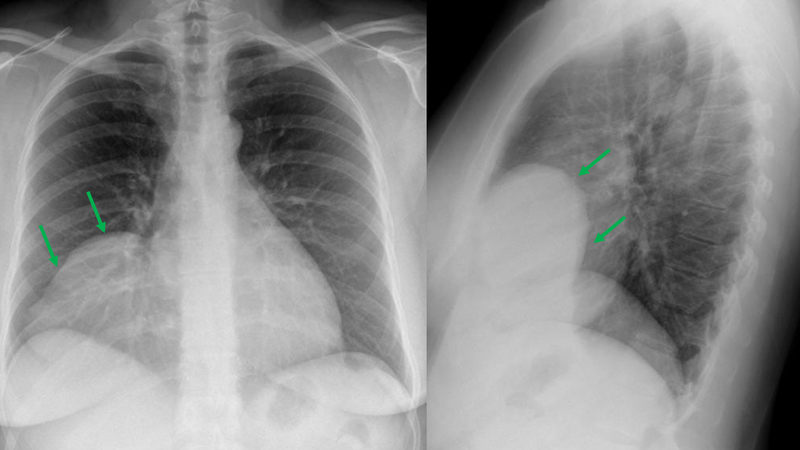

Nang màng ngoài tim bao gồm lá thành và lá tạng, tạo nên một khoang màng ngoài tim chứa khoảng 30 - 50ml dịch. U nang màng ngoài tim thường là kết quả của quá trình hình thành các khoảng cách, thường không gây ra triệu chứng trừ khi khối nang to dần lên, do đó nó chèn ép các cơ quan lân cận. Chúng thường xuất hiện ở độ tuổi từ 30 - 40 tuổi trở lên, thường tìm thấy nhiều nhất ở góc cơ tim trước bên phải, nhưng có thể xuất hiện ở nhiều vị trí khác.

Nang màng ngoài tim là bệnh lý bẩm sinh phổ biến thứ hai trong bệnh lý u nang trung thất, chiếm gần 6% khối u trung thất và khoảng 33% các tổn thương nang trung thất. Triệu chứng thường gặp bao gồm ho mãn tính, đau ngực, cảm giác đè ép vùng sau xương ức và rối loạn nhịp tim. Một số triệu chứng ít gặp có thể bao gồm ngất tái phát, viêm phổi, suy tim sung huyết, nguy cơ đột tử do nguyên nhân tim mạch.